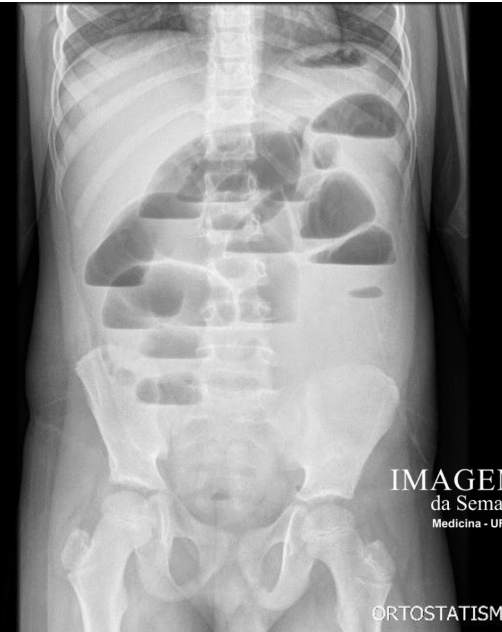

Q

Rotina de imagem de abdome agudo:

A

Tórax PA

Abdome AP ortostático

AP decúbito dorsal

Radiografia rotina no abdome agudo:

Raio x de tórax em PA Raio x de abdome em AP Radiografia de abdome em AP: decubito